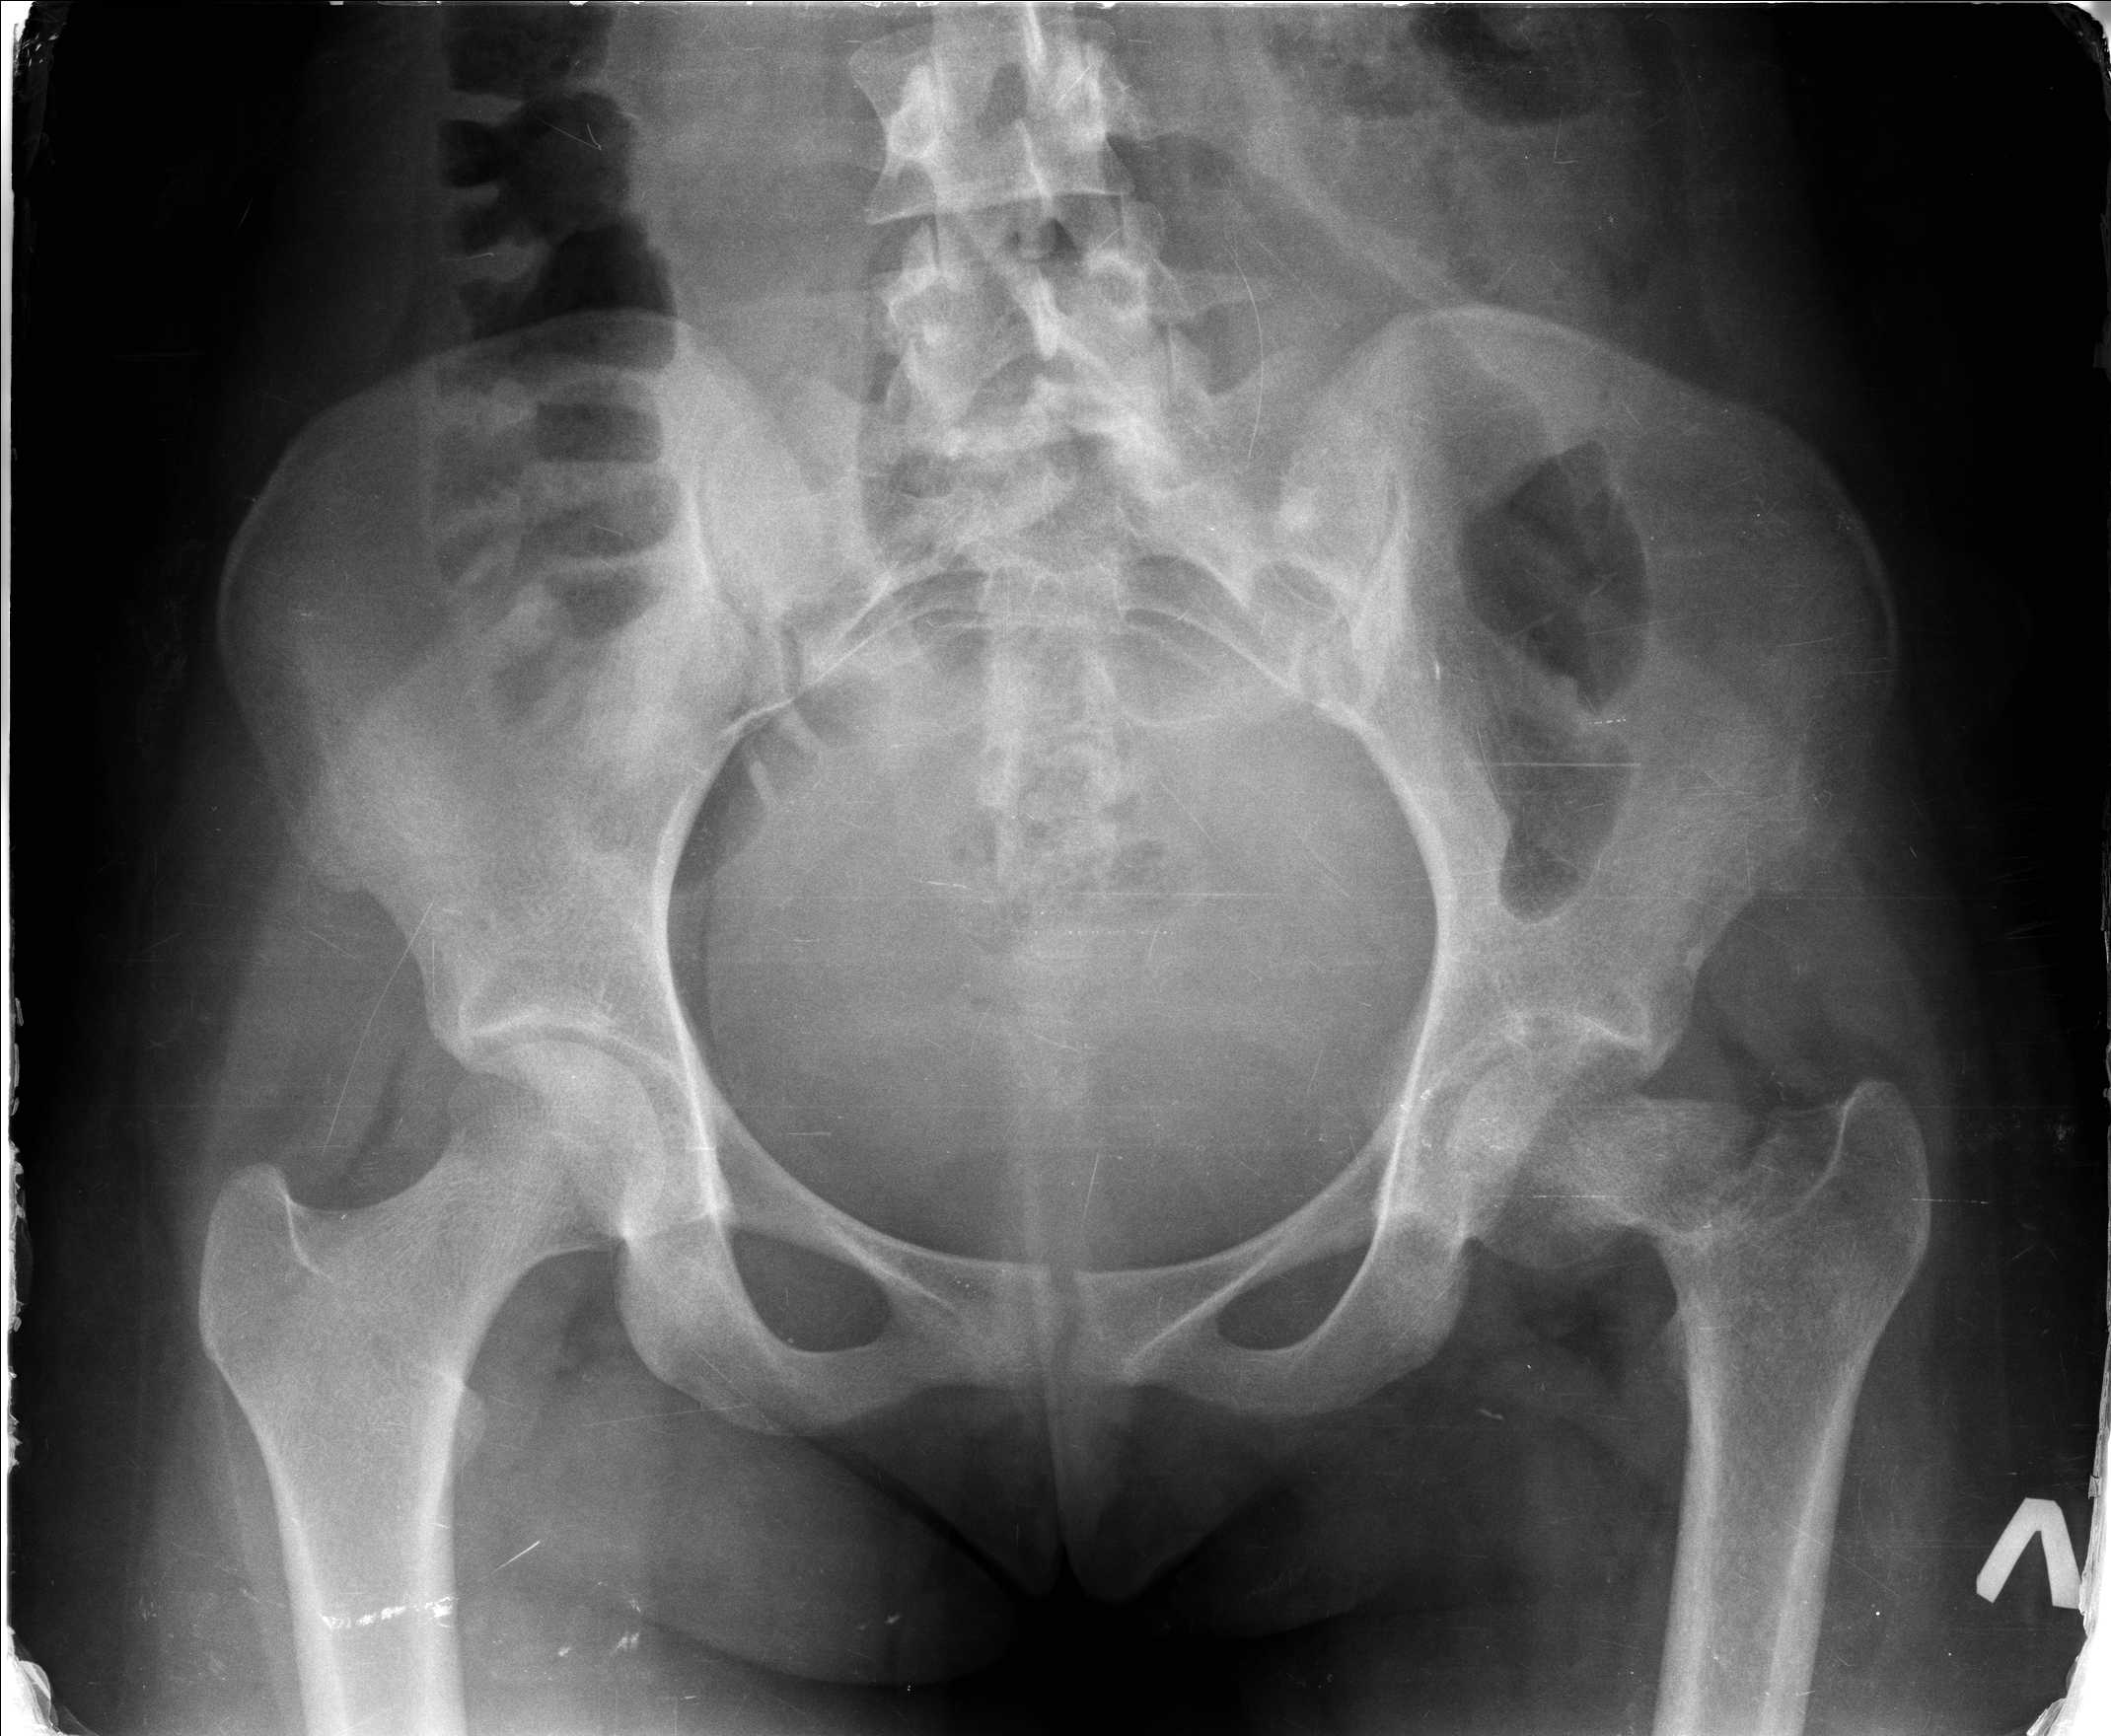

Добрый день уважаемые коллеги. Во такая ситуация. Девушка 19 лет травму получила в мае 2016г (изолированная травма, трансцервикальный перелом шейки левого бедра). Соматически здорова. Лечилась по месту жительства скелетным вытяжением в течении 1 месяца.

Затем переведена в наше учреждение. 18 июня выполнена операция, детали где , кто и как уточнять не имеет смысла( из протокола операции: выполнялась передняя артротомия, репозиция под визуальным контролем) . Учитывая характер выполненного остеосинтеза, после операции постельный режим 6 недель. Снимки в хронологии все выкладываю. КТ контроль сделан 2.09.16. для оценки состояния головки бедра. Помогите, определиться с дальнейшей тактикой.

Межвертельную остеотомию оптимально было сразу и делать. Сейчас еще длина потерялась, сползло бедро проксимально. Так что да, надо делать вальгизирующую остеотомию. А перед ней - закрытую репозицию, т.е. вернуть ситуацию ближе к той, что была при поступлении.